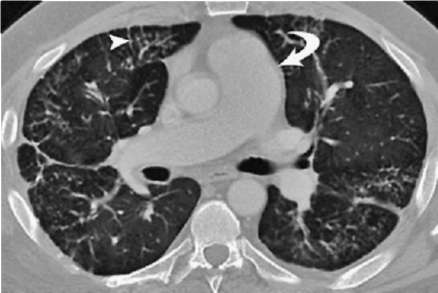

Лучевые методы исследования. Рентгенологическая картина при ЭТА зависит от стадии заболевания. В начальной фазе выявляются признаки отека интерстициальной ткани легких и распространенные мелкоочаговые затенения. При прогрессировании процесса формируются двусторонние изменения легочного рисунка по типу интерстициального фиброза, преимущественно в нижних отделах легких (рис. 2.28). В далеко зашедших случаях определяется мелко- и крупноячеистая деформация легочного рисунка. Описаны случаи, когда единственным рентгенологическим признаком болезни был односторонний плевральный выпот. Отсутствие каких-либо изменений на рентгенограммах отнюдь не исключает ЭТА. Так, при бериллиозе у 23-59% больных может выявляться умеренно выраженная двусторонняя лимфоаденопатия, а в ряде случаев - рентгенотрицательная форма бериллиоза (Dweik R.A., 2015). У 30% из 71 больных ЭТА, наблюдавшихся нами в клинике пульмонологии, в момент обследования изменений на рентгенограммах не было (Орлова Г.П., 2019). Группа больных ЭТА была обозначена условно как рентгенотрицательная группа. Уточнить диагноз помогает КТ легких, выявляющая интерстициальные изменения в легочной ткани по типу «матового стекла», усиление и деформацию легочного и сосудистого рисунка (рис. 2.29), фиброзные изменения тяжистого и звездчатого типов, на поздних стадиях - «сотовое легкое». ВРКТ выявляет «матовое стекло» и другие изменения в легочной паренхиме, которые не видны при обычном рентгенологическом исследовании. Но даже ВРКТ не всегда выявляет изменения в легочной ткани. Так, в 25% случаев гистологически подтвержденного хронического берил-лиоза легких ВРКТ была нормальной (Dweik R.A., 2013; Амосов В.И., Сперанская А.А., 2015; Amanullah S. et al., 2015).

Проведенное нами динамическое исследование КТ-паттернов у 42 больных ЭТА показало трансформацию отдельных типов интерстициальных пневмоний по мере прогрессирования патологического процесса в фиброзную НСИП или ОИП (рис. 2.30), что подтверждает объединительную концепцию интерстициальных пневмоний вне зависимости от этиологического фактора, которые являются не отдельными нозологическими формами, а стадиями течения фиброзирующего процесса в легких (Илькович М.М., Новикова Л.Н., 2018; Орлова Г.П. и др., 2019).